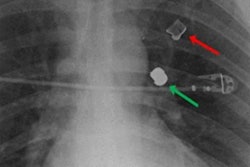

In contrast to injury patterns resulting from handguns, the patterns caused by AR-15 shootings are somewhat indescribable, Allen wrote. Bullets fired from these weapons exit the barrel at speeds three times faster and result in a cavitation effect on impact with the human body such that the bullet causes a ripple wave of destruction to arteries, veins, and soft tissues.

"Organs that experience high-velocity gun injury are left eviscerated. Bony structures that are directly impacted by these ballistic missiles are reduced to rubble. The exit wounds associated with AR-15 firearms are often the size of grapefruits. Simply put, when surgeons attempt life-saving measures in these cases, there is often nothing salvageable to fix," Allen wrote.